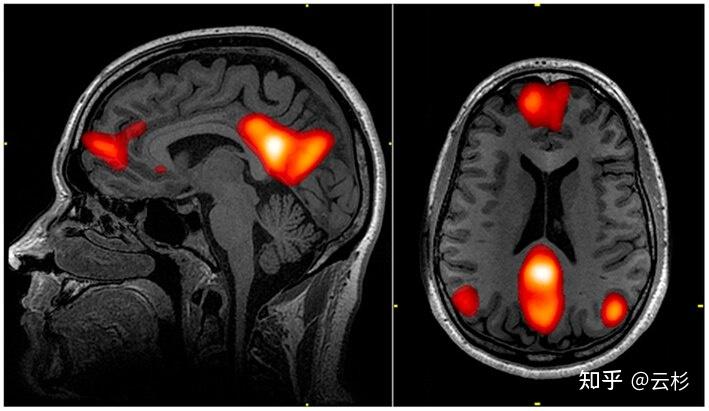

学者们把这部分持续活跃的功能性神经网络称作默认模式网络(Default Mode Network,DMN):

DMN 负责内部思考、计划、情绪、记忆整合,一直在运转。

除了维持 DMN 外,静息状态下的大脑还要维持神经元膜电位、支持突触活动,让脑神经长期处于待命状态。